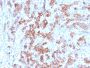

Applications IHC

IHC, FFPE (verified)

PC3, BT474, HepG2, HDLM-2 or Daudi cells. Tonsil, lymph node or spleen.

IHC (FFPE) (verified)